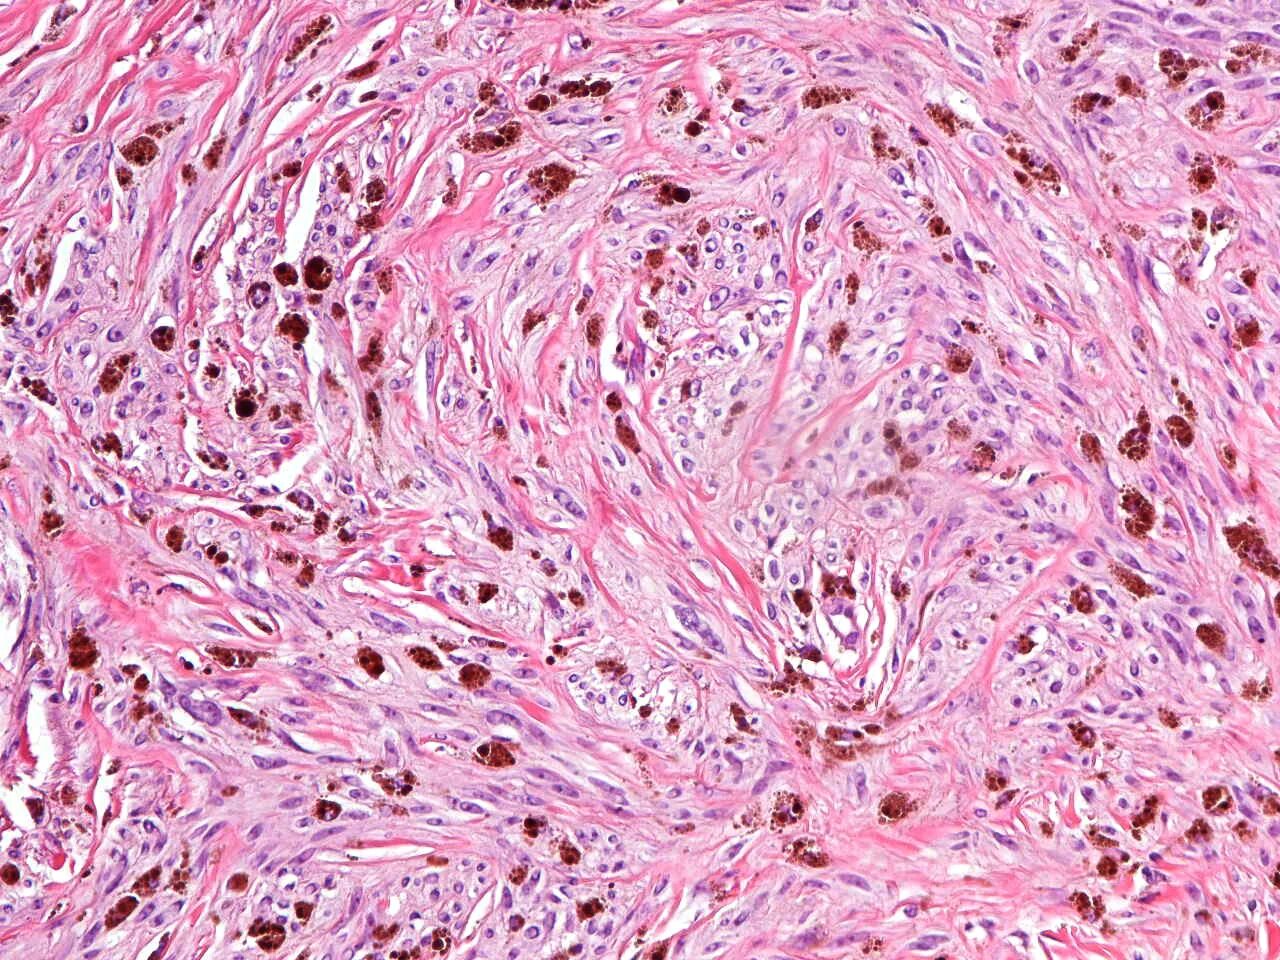

Гистология фото